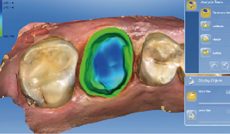

數位印模

透過 CEREC Omnicam 口內取像鏡頭

以光學取像原理擷取患者口腔環境資訊

避免傳統印模材造成的變形及誤差

提供假牙贗復更為精準且快速的印模方式

完整的設計功能